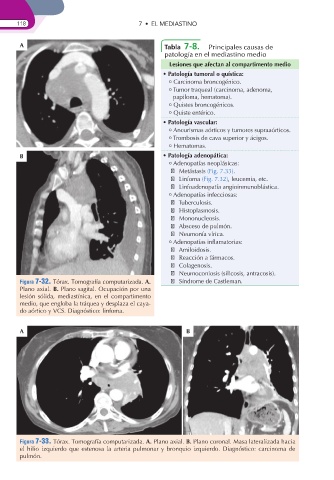

Figura 7-32. Tórax. Tomografía computarizada. A. Síndrome de Castleman.

Plano axial. B. Plano sagital. Ocupación por una

lesión sólida, mediastínica, en el compartimento

medio, que engloba la tráquea y desplaza el caya-

do aórtico y VCS. Diagnóstico: linfoma.

Figura 7-33. Tórax. Tomografía computarizada. A. Plano axial. B. Plano coronal. Masa lateralizada hacia

el hilio izquierdo que estenosa la arteria pulmonar y bronquio izquierdo. Diagnóstico: carcinoma de

pulmón.